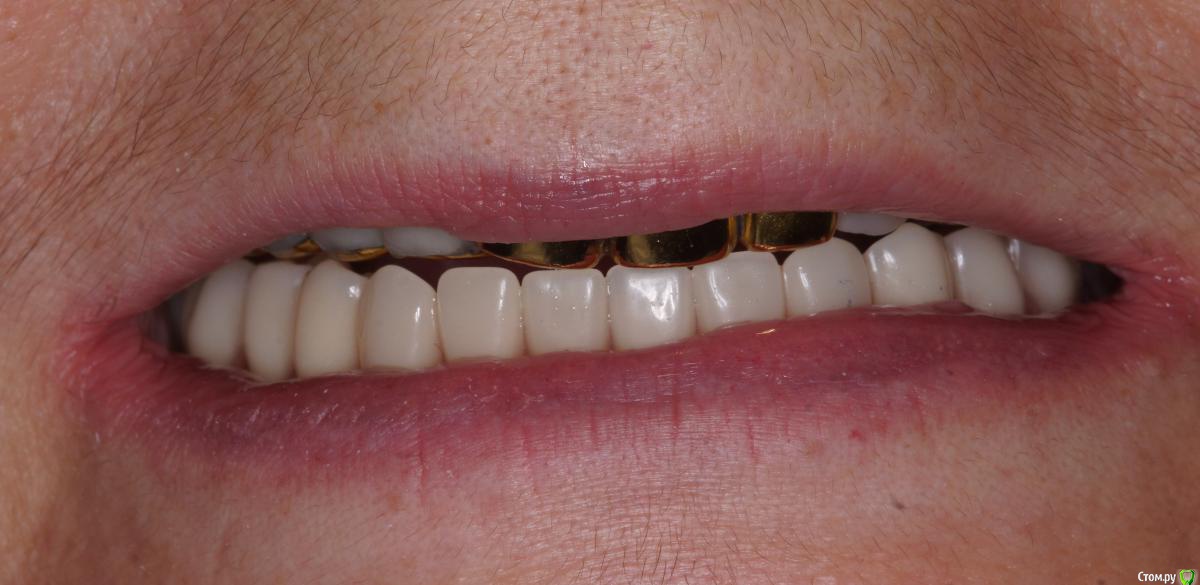

Во рту post-36568-0-13353100-1566455461_thumb.jpg post-36568-0-30978400-1566455479_thumb.jpg

Панорама post-36568-0-16435400-1566455538_thumb.jpg как будто дистально балка прилегает хуже, но все держится без втулок. Пока что делать ничего не буду, понаблюдаем.